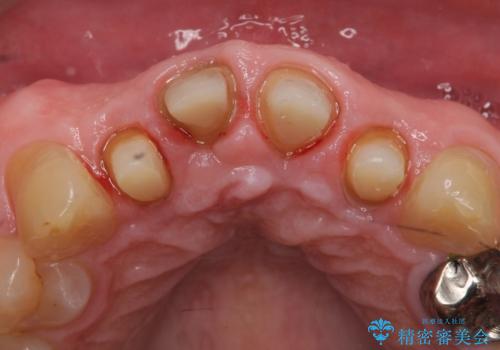

- 前歯の見た目が気になるといらっしゃった方の症例です。

再根管治療後、オールセラミッククラウンによる補綴を行いました。

右上2は歯茎のラインを整えるため歯周外科を行っております。